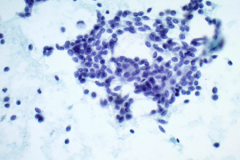

Aspirates of MTC are moderately cellular, showing a single cell pattern with occasional clustering and small aggregates. Cytologically, tumor cells can appear plasmacytoid, polygonal, or with spindle cells. Cells are uniform in size, but rare large pleomorphic cells may be present. The chromatin shows a coarse, granular, neuroendocrine pattern with inconspicuous nucleoli. Intranuclear inclusions may be seen, and nuclear grooves are rare. The cytoplasm is granular, and the amount is variable and rarely scant. Cytoplasmic dendritic processes may also be seen. Amyloid may be present in the background, although it can be identical to colloid in Papanicolaou-stained specimens. Variants of MTC include a follicular variant, papillary variant, small cell variant, giant cell variant, and a clear cell variant7. Cell blocks of MTC typically stain positive for calcitonin, CEA, TTF1, synaptophysin, and chromogranin, and are negative for thyroglobulin and PAX-88,9.

The tumor cells of this case presentation posed a diagnostic challenge due to their divergence from the typical cytological appearance of MTC. The majority of tumor cells had scant cytoplasm, including cells that resembled naked nuclei and cells with a plasmacytoid appearance. A diagnosis of MTC was rendered in conjunction with the patient’s elevated calcitonin level, history of MTC and MEN2, and comparison to the patient’s previous two MTC diagnoses.